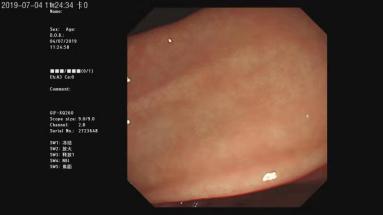

①胃镜

正常十二指肠

正常胃体

正常胃角

正常食管

反流性食管炎

霉菌性食管炎

食管CA

胃角溃疡